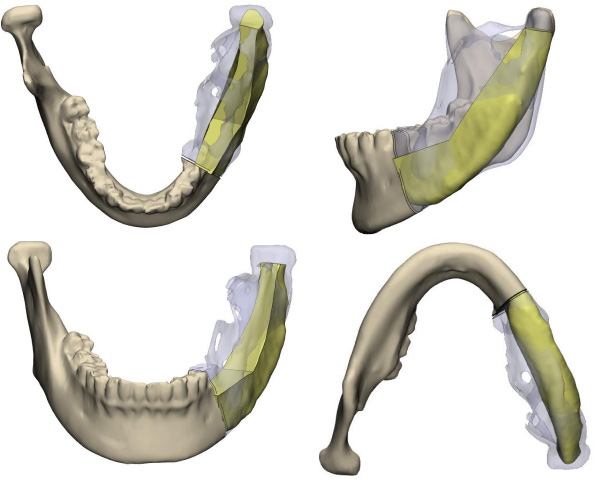

頜骨外形不規(guī)則,將髂骨塑形為下頜骨的形狀非常困難,稍有誤差,不但影響患者外形,還會出現(xiàn)咬合紊亂的情況……這是一臺只許成功不許失敗的手術(shù),所有環(huán)節(jié)都容不得一點馬虎,為了能夠精細塑形,口腔科專家采用了先進的3D模擬技術(shù)制作出各個截骨引導(dǎo)板,在術(shù)前進行多次模擬重建手術(shù),確保萬無一失。

手術(shù)當天,口腔科手術(shù)團隊首先按照術(shù)前設(shè)計并3D模擬的截骨導(dǎo)板對下頜骨及腫瘤精準切除;再根據(jù)術(shù)前設(shè)計的髂骨截骨導(dǎo)板精準取骨和精準切割塑形拼接,后把移植骨的動脈和靜脈在顯微鏡下吻合到頸部的動脈和靜脈血管上,重建血循環(huán),恢復(fù)功能,經(jīng)過十多個小時的努力,終于圓滿完成了下頜骨缺損重建。